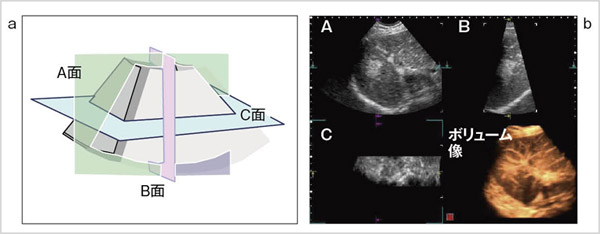

図3は,4D造影超音波モードのMPR(Multi Planer Reconstruction)表示の例である。図3 aに示すとおり,走査方向をA面,揺動方向をB面,体表に平行面をC面と定義する。図3 bは,ソナゾイド投与下の早期相であり,直交3断面の造影像と,右下に動脈血流のボリューム像が表示されている。

図3 超音波造影モードのMPR像

図3 超音波造影モードのMPR像 (画像ご提供:癒しの森消化器内科クリニック・小井戸一光先生)